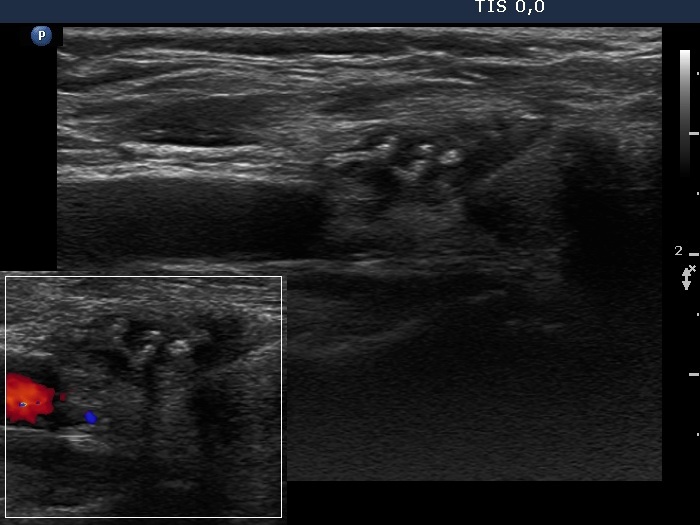

Granulation around surgical thread (histological diagnosis) - case 411 |

Papillary carcinoma (histological diagnosis) - case 779 |

Here is another example of the differential diagnostic problem caused by granulation around surgical thread. Again, there is no difference between the ultrasound presentations of these cases except for the vascularization. The right, malignant case cannot be a granulation around surgical thread which is always avascular; however, this is not a great revelation in a patient who has not been operated. Conversely, the lack of vascularization by no means excludes the possibility of a carcinoma.